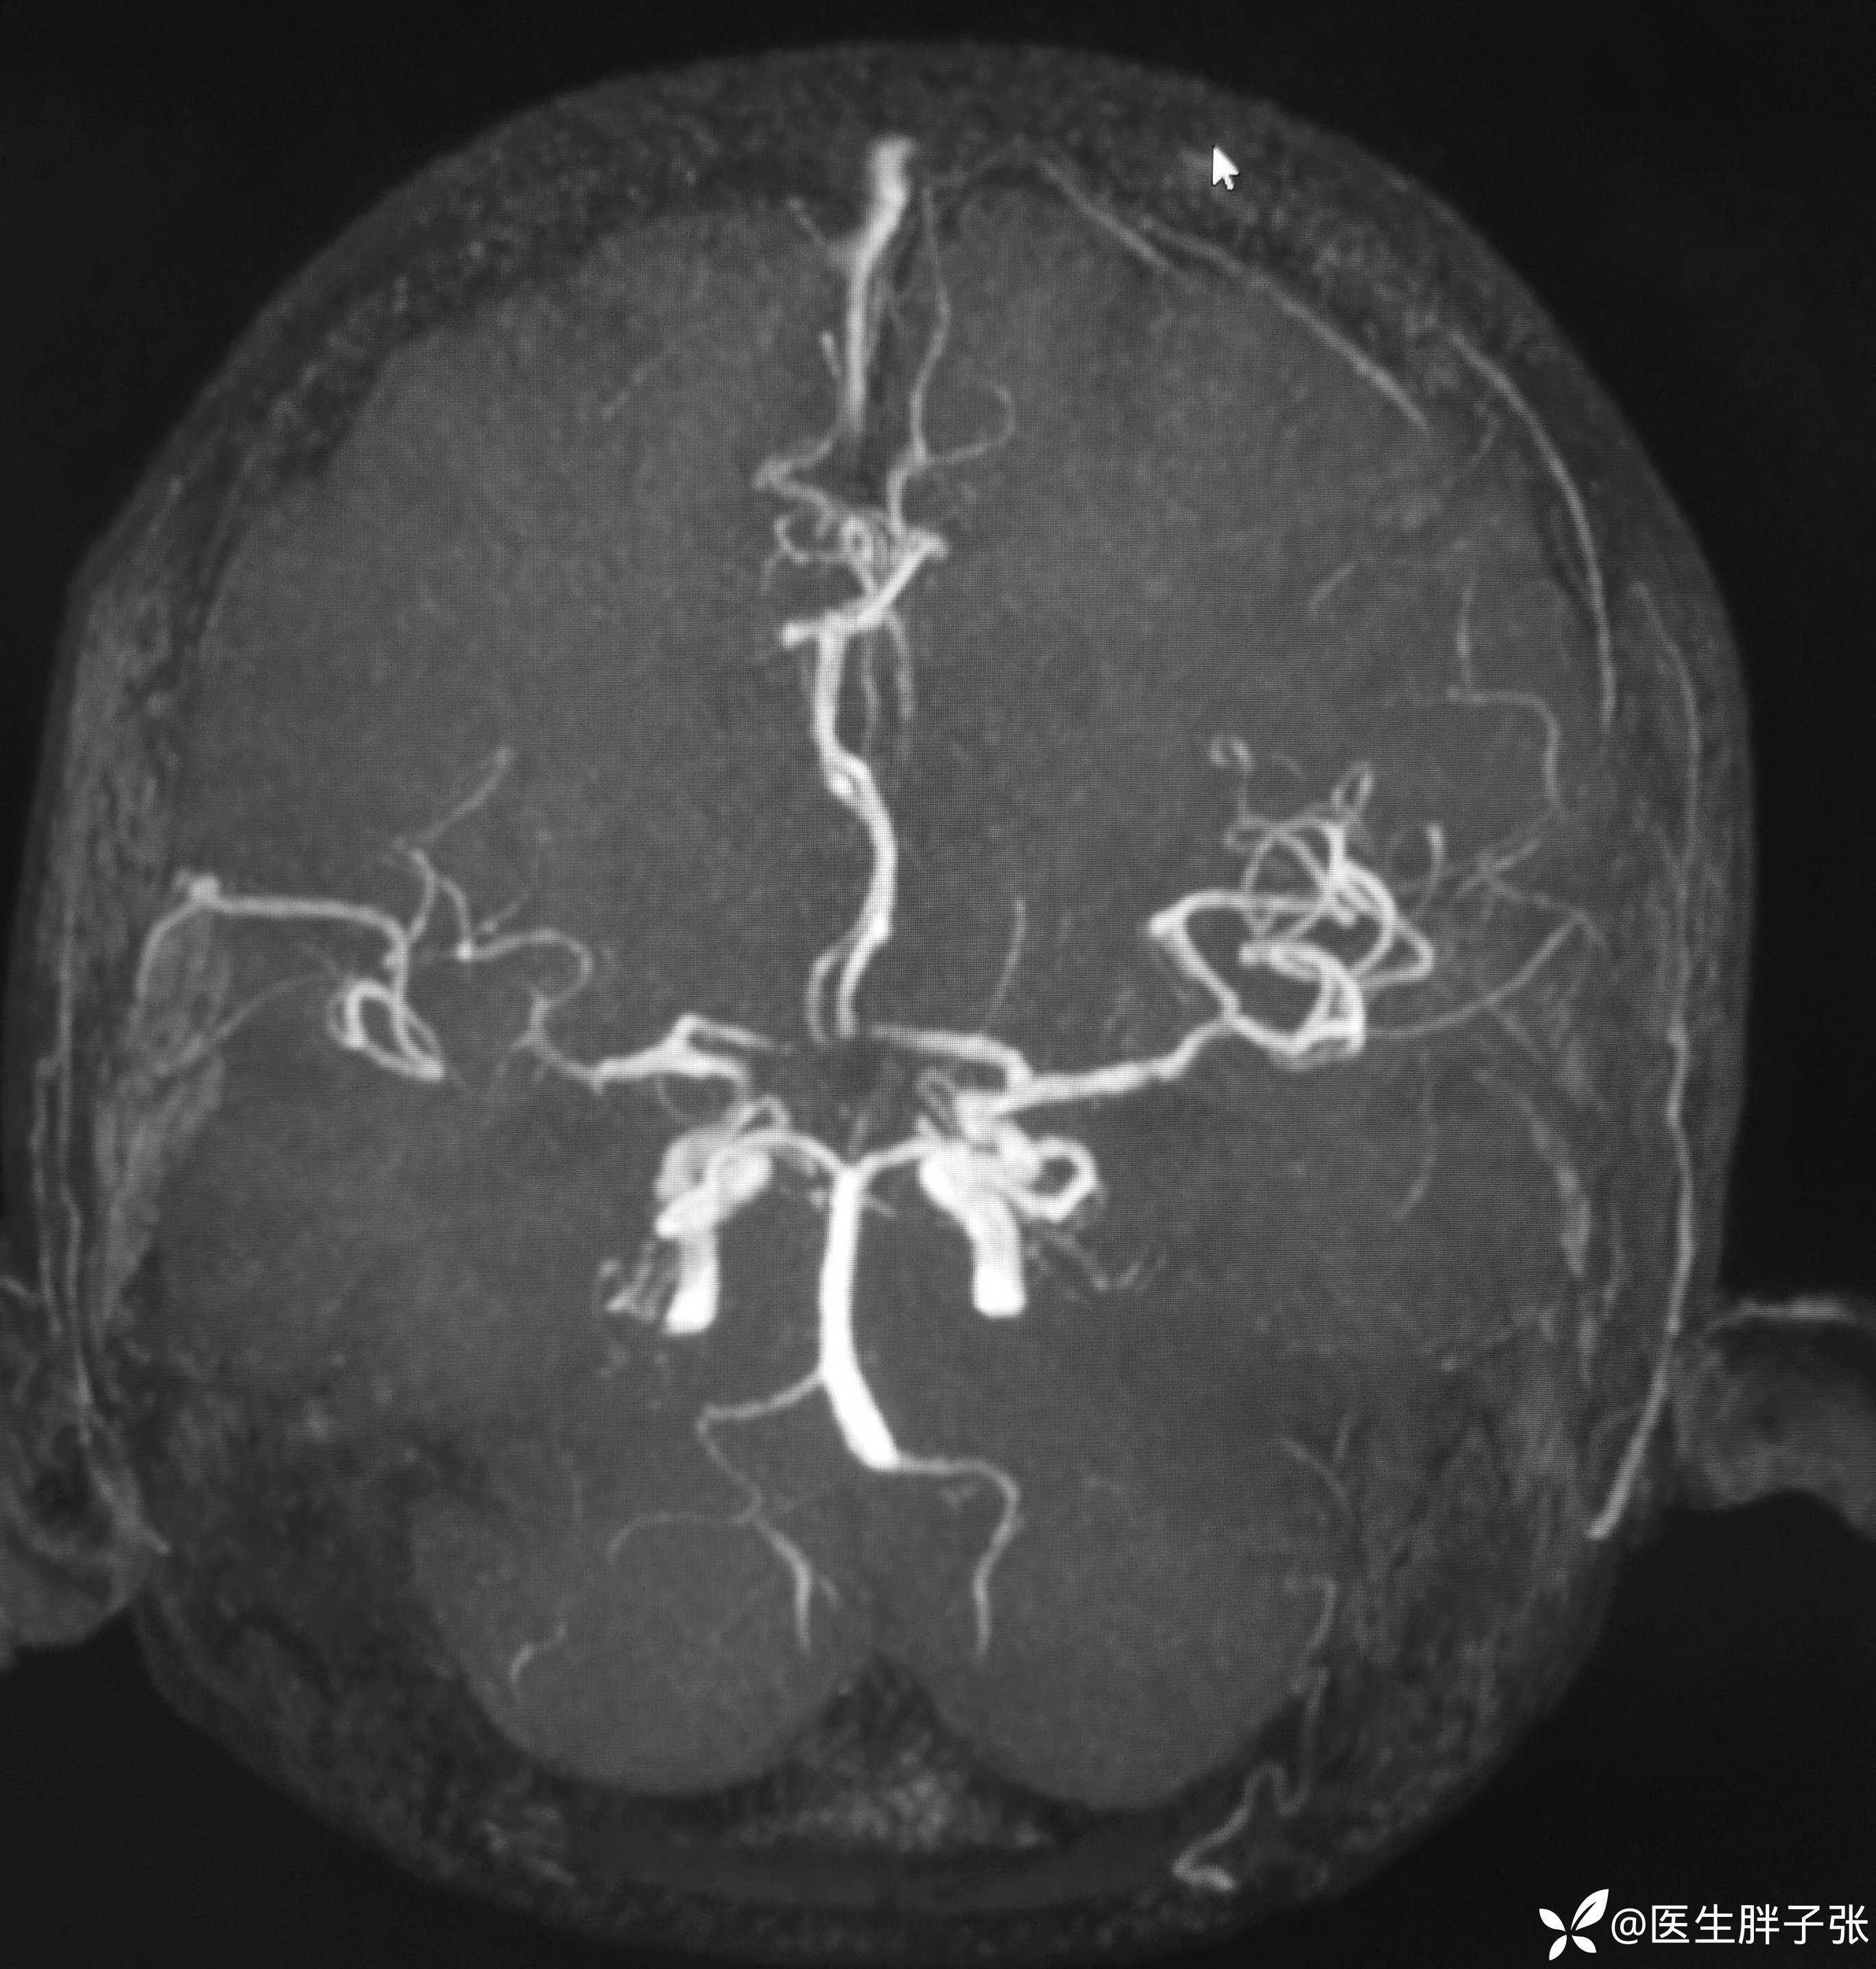

颅脑MR:右侧颞叶新近梗死灶;老年性脑改变;右侧大脑中动脉部分M2段及以远未见显示,建议头颈部CTA检查。

溶栓过程顺利,无并发症。患者发病前有腹泻,MRA提示右侧大脑中M2闭塞可能